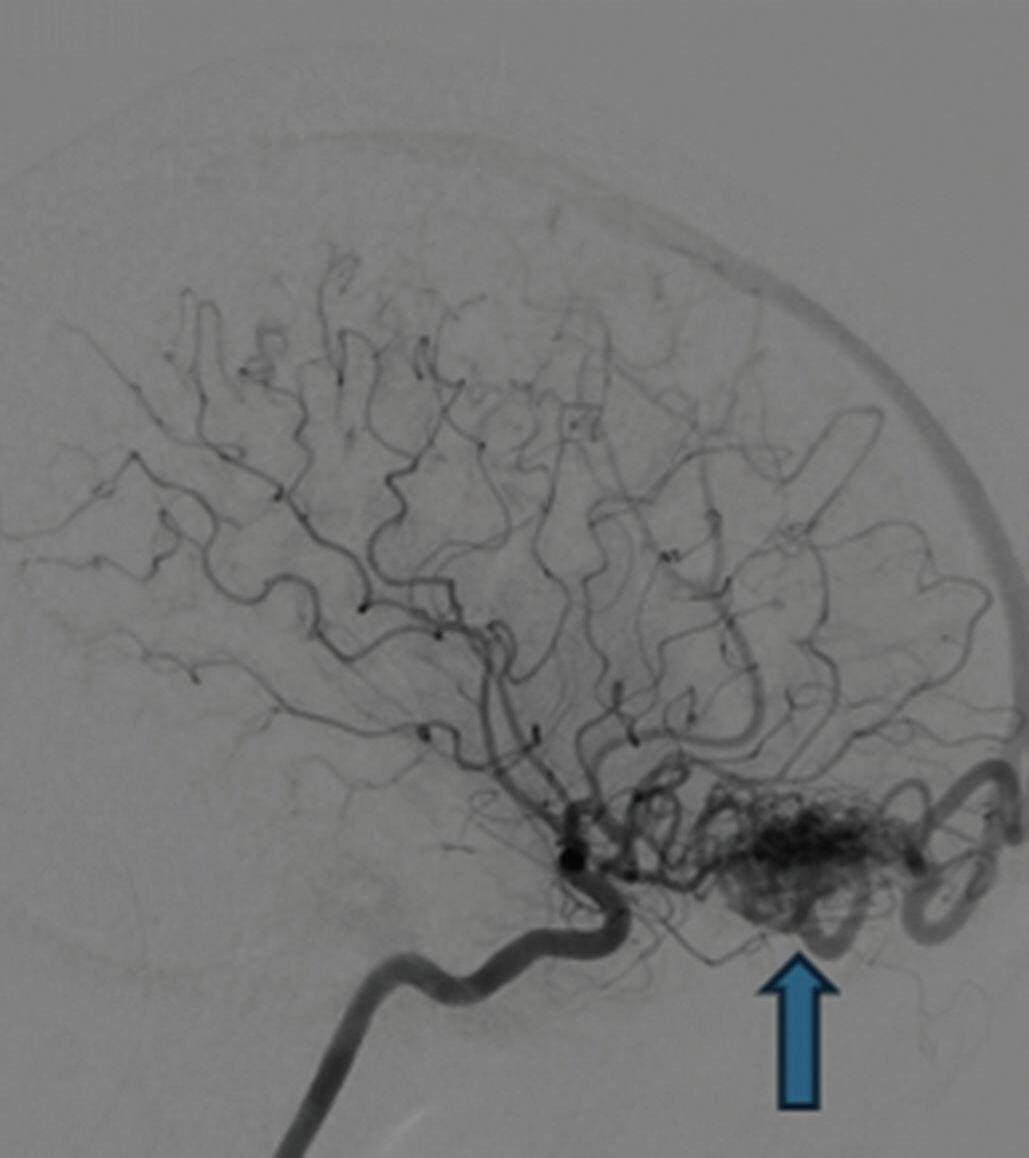

Com relação ao fluxo no interior do nidus, alguns autores classificam-nas em alto fluxo (Fig. 1-8) e baixo fluxo (Fig. 1-9). São consideradas de alto fluxo aquelas em que a opacificação após injeção de contraste ocorre apenas na malformação, em contrapartida, nas de baixo fluxo, ocorre opacificação da MAV e de outras artérias normais do mesmo território vascular. Exemplificando as lesões de alto fluxo temos as malformações arteriais, as malformações arteriovenosas e as fístulas arteriovenosas, enquanto as lesões de baixo fluxo são representadas pelas malformações venosas, linfáticas e capilares.25

Fig. 1-8. (a-c) RNM T1 com contraste, cortes sagital (a), coronal (b) e axial (c) demonstrando MAV não rota com nidus localizado no lobo occipital à esquerda (setas longas). (d) Arteriografia digital cerebral com injeção de contraste via carótida direita (AP) mostrando a contribuição da carótida direita na irrigação da MAV contralateral. (e,f) Com injeção de contraste via carótida esquerda, em Perfil e AP respectivamente, observa-se nidus compacto nutrido por ramos da artéria cerebral média à esquerda e a veia de drenagem precoce se dirigindo para o seio sagital superior. Projeções em AP (g) e em perfil (h) demonstrando a contribuição do sistema vertebrobasilar por meio de ramos distais da artéria cerebral posterior à esquerda e drenagem para os seios sagital superior e sigmoide à esquerda (setas curtas).